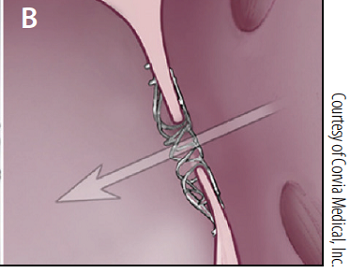

- -- transcatheter edge-to-edge device (TEER)

Eventually, the leaflets no longer fully close after each pumping action, allowing blood to jet backwards through them from the ventricle back into the atrium. This is the mitral regurgition (MR). (In the diagram at the upper left, a healthy mitral valve at the top is compared with a damaged valve below.)

(In the image at right, the red spurt of blood is shooting upward and backward, from the left ventricle, through the not-fully-closed mitral valve, back into the left atrium.)